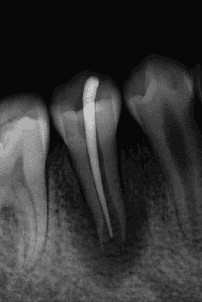

过牙髓再生治疗,促进牙髓坏死的年轻恒牙牙根进一步发育,牙髓活力测试呈阳性 。

术后1